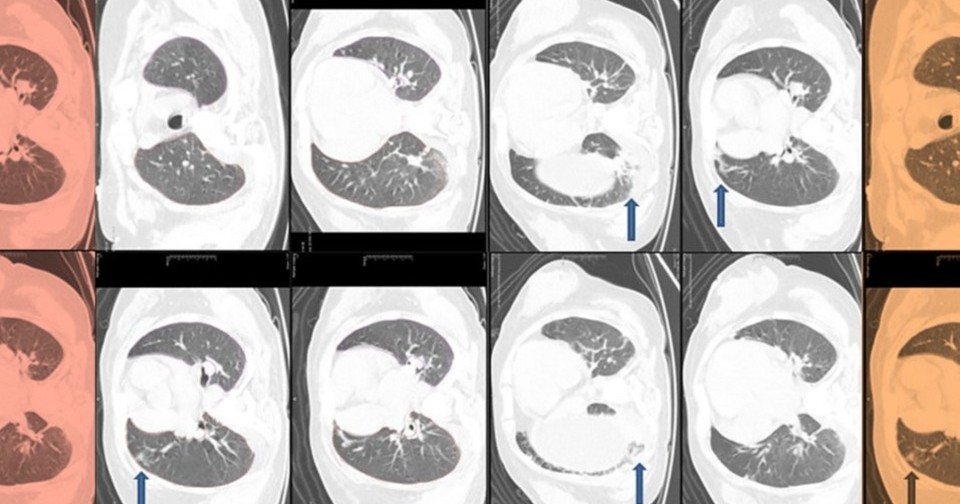

Анализ костного мозга подтвердил неэффективный эритропоэз без признаков злокачественности. Однако тяжесть клинических проявлений не соответствовала одному только дефициту питательных веществ. Ультразвуковое исследование брюшной полости выявило увеличение печени со стеатозом и циррозом. Аутоиммунные и инфекционные причины гепатита были исключены. На компьютерной томографии в обоих легких было отмечено диффузное помутнение по типу матового стекла с множественными фиброзными и ателектазными изменениями. Также врачи обнаружили вторичный гиперпаратиреоз с дефицитом витамина D и остеопорозом. Такой набор симптомов натолкнул врачей на поиск синдромальной генетической патологии.